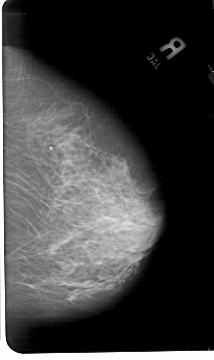

A_1496_1.RIGHT_MLO

RIGHT_MLO LINES 5491 PIXELS_PER_LINE 3361 BITS_PER_PIXEL 12 RESOLUTION 43.5 NON_OVERLAY